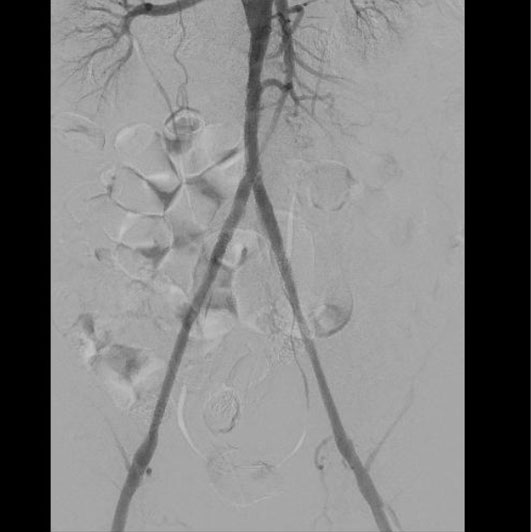

Пациенту была выполнена высокотехнологичная миниинвазивная эндоваскулярная операция – баллонная ангиопластика и стентирование брюшного отдела аорты, левой и правой подвздошных артерий, с хорошим результатом, с полным восстановлением прямого кровотока на всем протяжении обеих нижних конечностей. Данная операция миниинвазиваная, длилась 2.5 часа, была выполнена через 2 маленьких прокола в руке и ноге под местной анестезией и является альтернативой большой и долгой полостной операции, с разрезом брюшной полости под общим наркозом, которые чаще всего выполняются при таком сложном поражении.